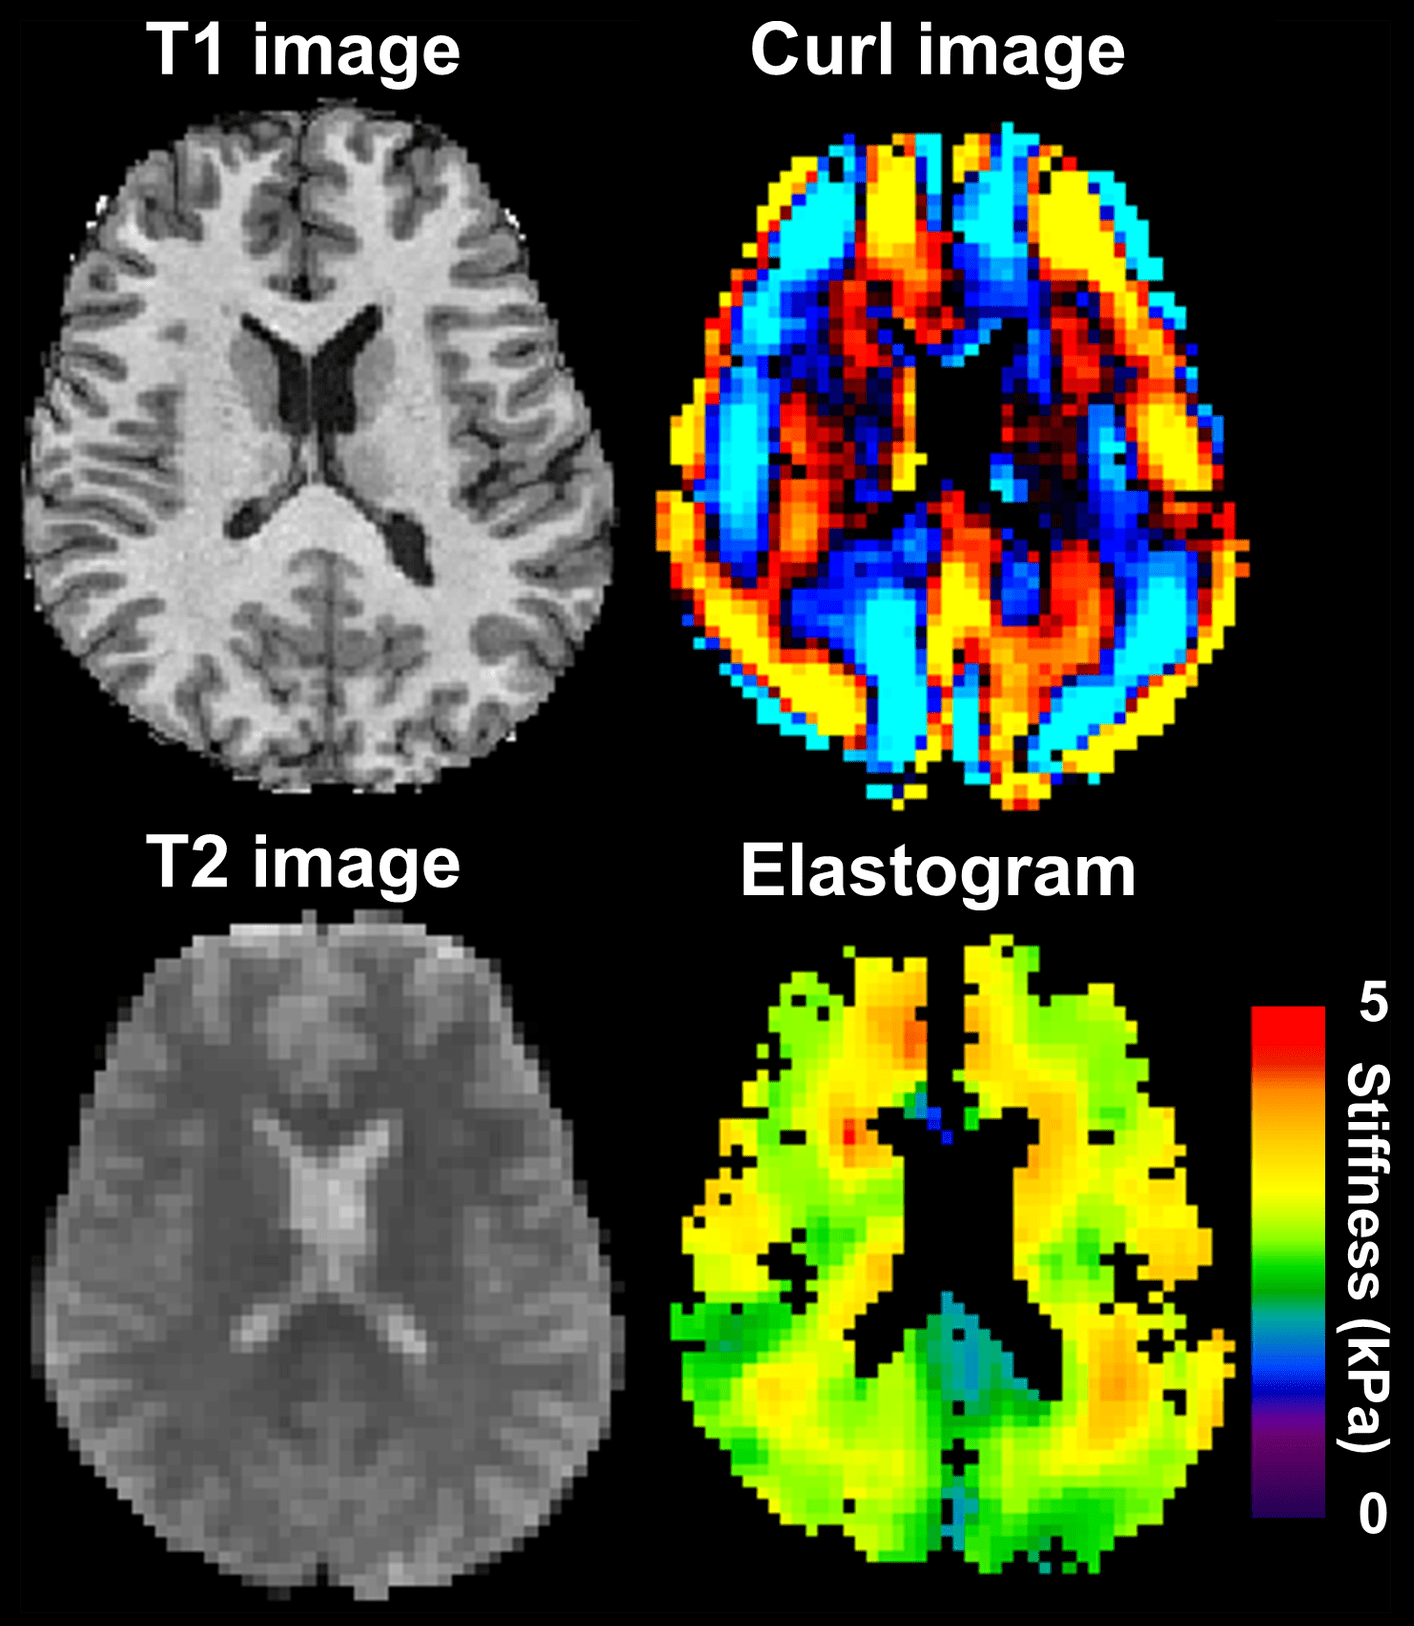

Обикновено се измерват няколко параметъра, чрез разделяне на честотните колебания на сектори, които са носители на определени физиологични свойства и информация. Честотата на мозъчните вълни показва броя осцилации за една секунда, а целта на ЕЕГ е да проследи евентуални отклонения от клинично значимите честотни интервали.

Евентуални отклонения биха могли да бъдат идентифицирани с изследване на количествена енцефалография, която показва точните стойности.